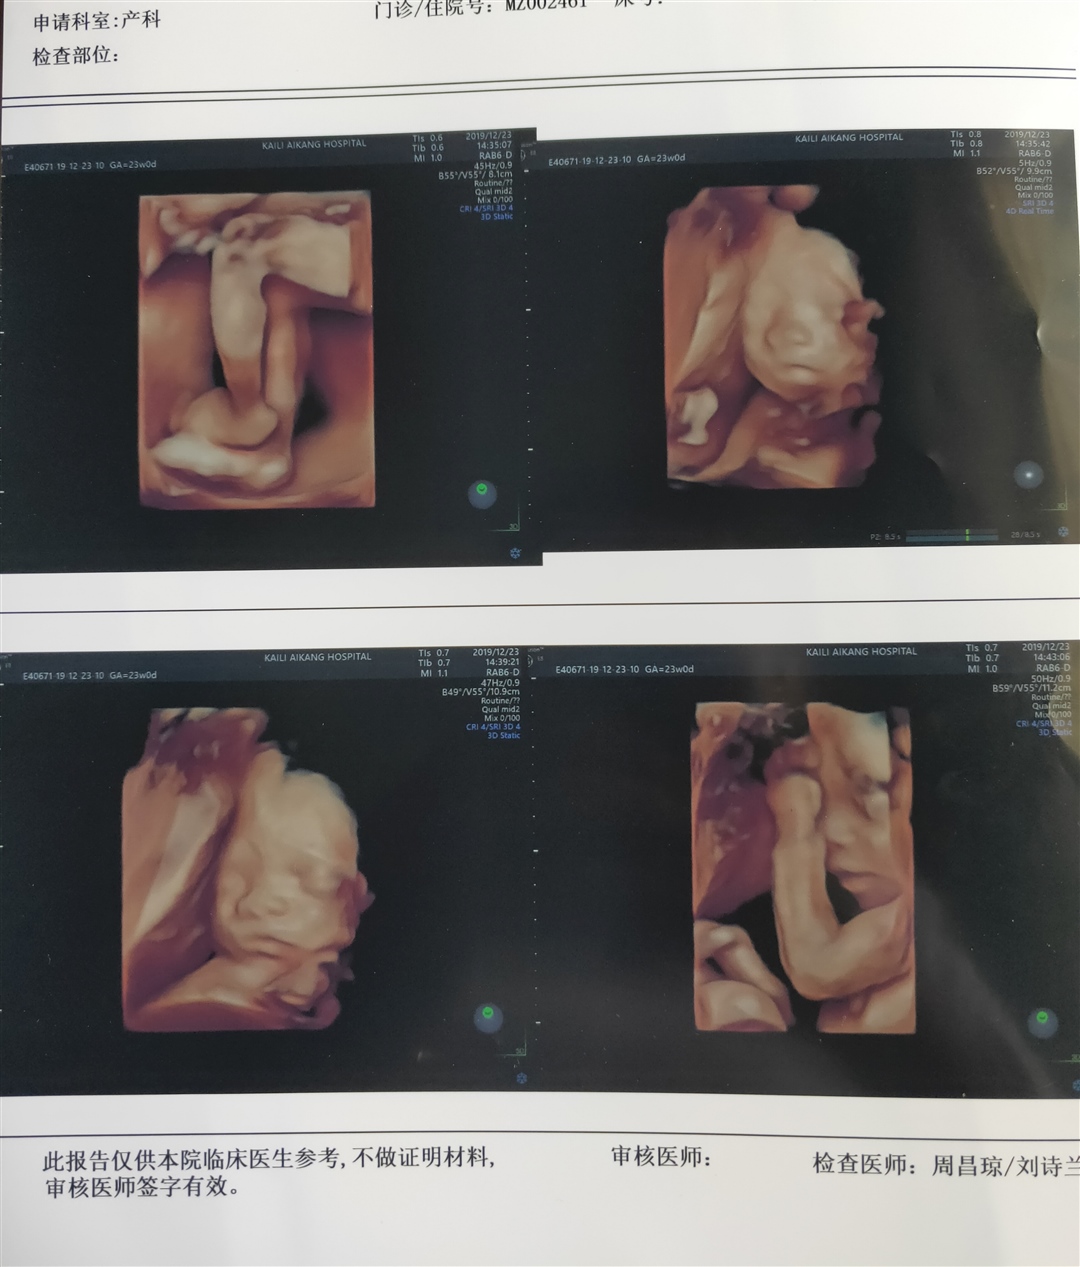

宝宝10个月19天

宝7个月